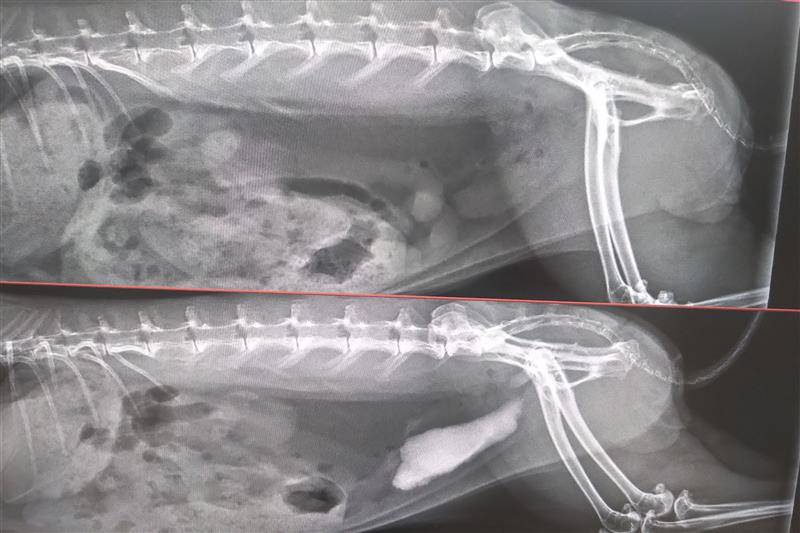

Röntgenbild von Kaninchen mit verkalktem Nierenbecken (links) und Harnleiterstein (rechts)

Leider begünstigt der besondere Kalziumstoffwechsel des Kaninchens die Bildung von Harngrieß und Harnsteinen. Denn bei Kaninchen wird Kalzium nicht, wie bei anderen Tieren, nach Bedarf aus dem Darm resorbiert und das überschüssige Kalzium mit dem Kot ausgeschieden, sondern es wird zunächst alles Kalzium resorbiert und das Überschüssige wird dann in der Niere aus dem Blut gefiltert und über den Harn abgegeben. Dadurch wird Kalzium beim Kaninchen fast ausschließlich über die Harnwege ausgeschieden, bei denen es auch einige Engpässe und somit ideale Ablagerungsstellen zu bewältigen gilt. Dazu kommt, dass der pH von Kaninchenurin, wie bei allen pflanzenfressenden Tieren, alkalisch ist, also über dem Neutralwert von 7. Dieser pH-Wert begünstigt die Kristallausfällung von Kalzium im Harn. Bei dieser Kalziumablagerung entsteht dann der sogenannte Grieß, der sich in der Harnblase sammeln oder zu Steinen in den Harnleitern (führt von der Niere zur Harnblase), Harnröhre (führt von der Harnblase bis zum Ausgang) oder Nieren bzw. Nierenverkalkung (siehe Röntgenbild) führen kann.

Konnten Harnsteine oder eine verkalkte Niere im Röntgenbild festgestellt werden, muss abgeklärt werden, wie funktionstüchtig die Nieren noch sind und ob sie eventuell schon Schaden genommen haben. Die Nierenwerte werden mittels Blutuntersuchung überprüft.